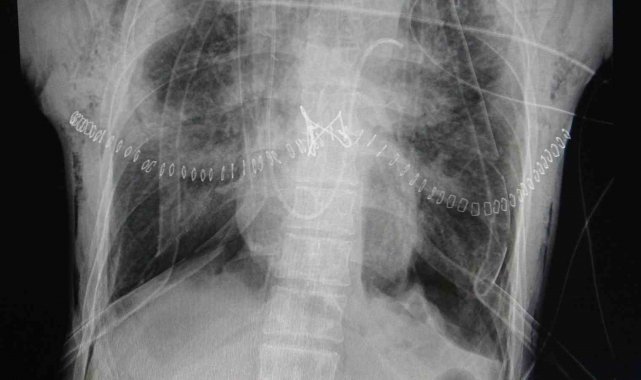

Gastroenteroloji Cerrahisi Uzmanı Prof. Dr. Mustafa Duman, "Hastanemiz, üst düzey cerrahi hizmetlerin yanı sıra organ nakli konusunda da önemli bir merkez. Hastanede kalp nakli, akciğer nakli ve karaciğer nakli işlemleri başarıyla gerçekleştiriliyor. Dün, hastanede ilk kez aynı gün içerisinde hem akciğer hem de karaciğer nakli yapılmasıyla önemli bir başarıya imza atıldı. Genç bir hastanın hayatını kaybetmesi üzücü bir olay olmasına rağmen, organlarıyla dört kişiye umut oldu. Akciğer ve karaciğer, hastanede organ bekleyen iki hastaya nakledildi. Donörün böbrekleri ise başka bir merkezde iki hastaya hayat verdi. Keşke insanlar hiç ölmeseler. Ama eğer ölüm gerçekleştiyse, ardından başka hayatlara umut olmak, insanlara hayat vermek mümkün. Bu büyük bir iyilik ve örnek davranış. Organ bağışı konusundaki hassasiyetin artmasını diliyorum." diye konuştu.